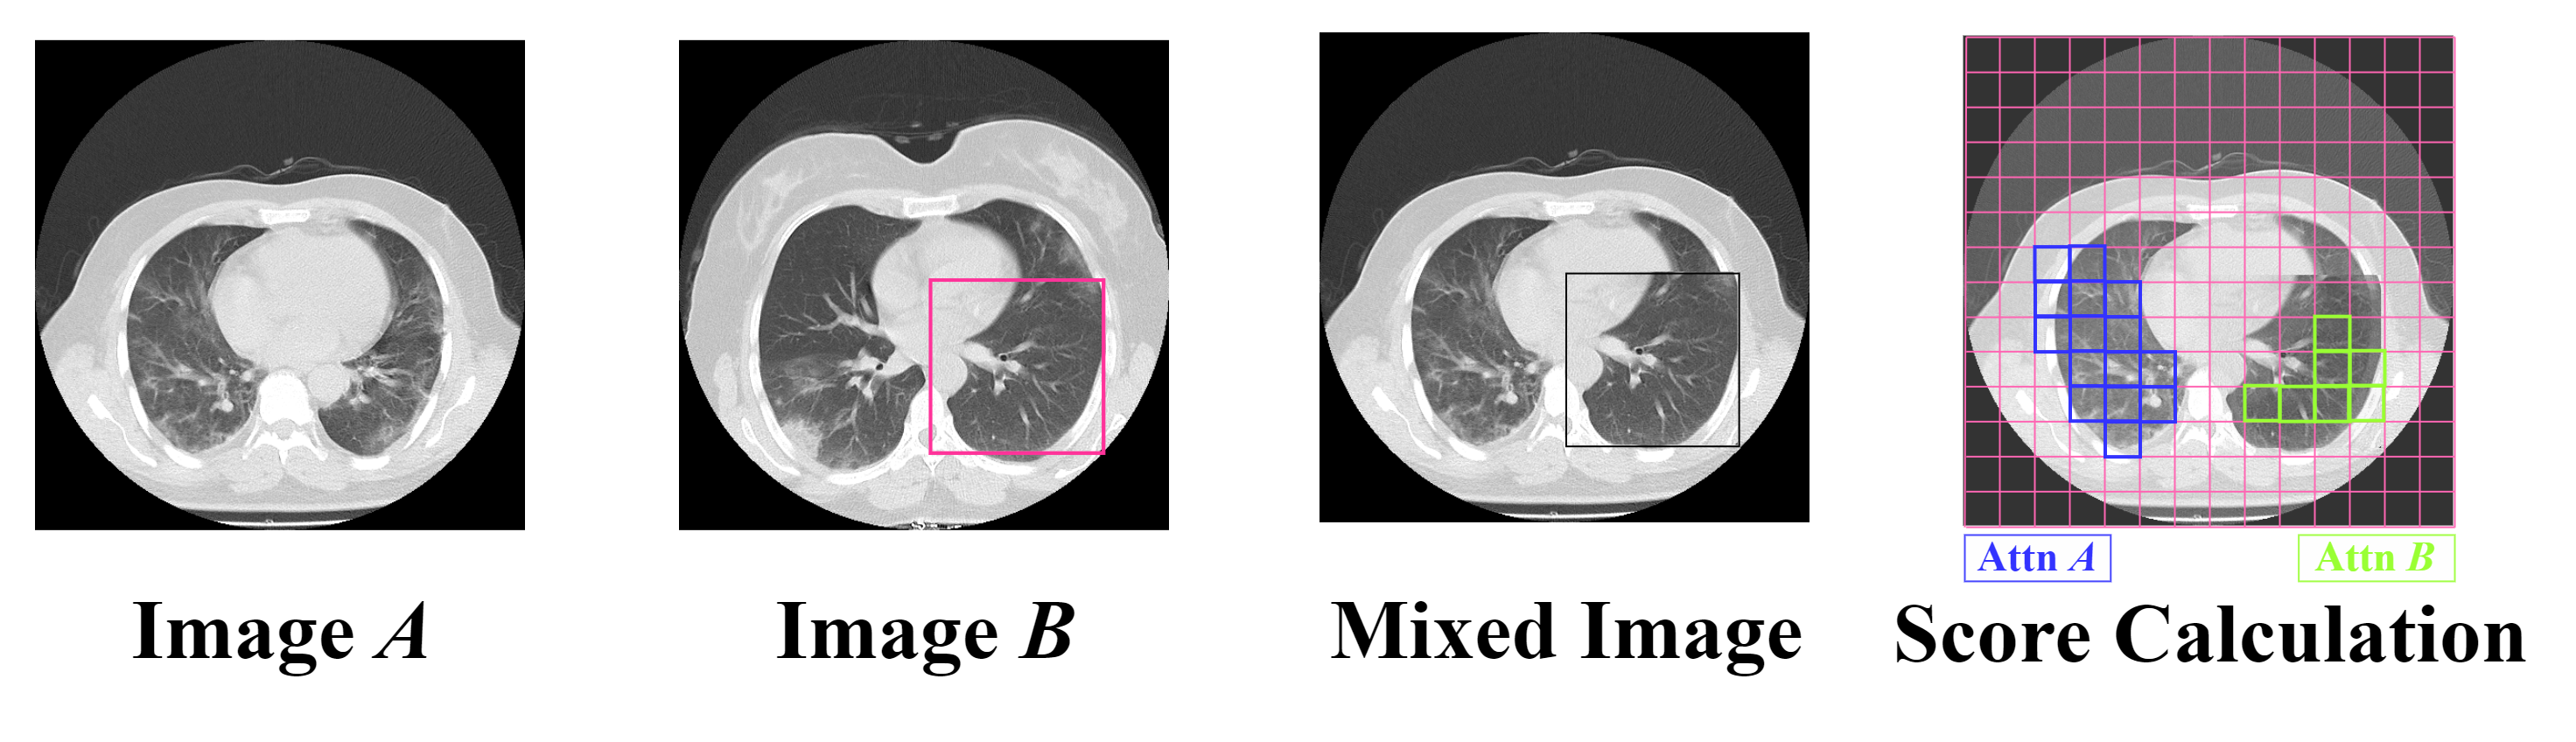

3.2 Data Augmentation: Conditional Online TransMix

In our work, we have addressed the problem of score imbalance in pneumonia severity infection datasets by using an online augmentation technique based on the TransMix method [13]. Although this technique was originally proposed for classification tasks, we have adapted it for regression by generating new mixed scores for the newly mixed images. Our novel adaptation of this data augmentation technique leverages attention maps to drive the score mixing process. The mixed image is obtained using the traditional CutMix method [60], where a random patch of image is inserted into image to form a new mixed image, as shown in Figure 3. After creating the mixed image, its relative ground truth score is calculated following the TransMix approach. This method assigns mixed labels based on a multi-head class attention map computed using self-attention mechanisms similar to those used in ViTs. The class attention map of the augmented image represents the attention of the class token (CLS) to the input patches of the mixed image and highlights the most useful patches of the input image for the final prediction.

TransMix uses this attention map to control the process of mixing scores. In this context, (representing the proportion of the source image) is set to the sum of the weights in the attention map that overlaps with the clipping mask, each weight corresponding to the importance assigned to a particular region of the image.

Given images and , we update the mixing coefficients using the attention map of the mixed image :

| (4) |

where represents nearest-neighbor interpolation that downsamples the mask from into pixels.

In this way, we can dynamically reassign the weights of the scores depending on how much attention map is directed to each patch. The patches that receive more attention have a higher proportion of the [13]. The ground truth score of the mixed image is:

| (5) |

where and are the ground truth scores of images and respectively.